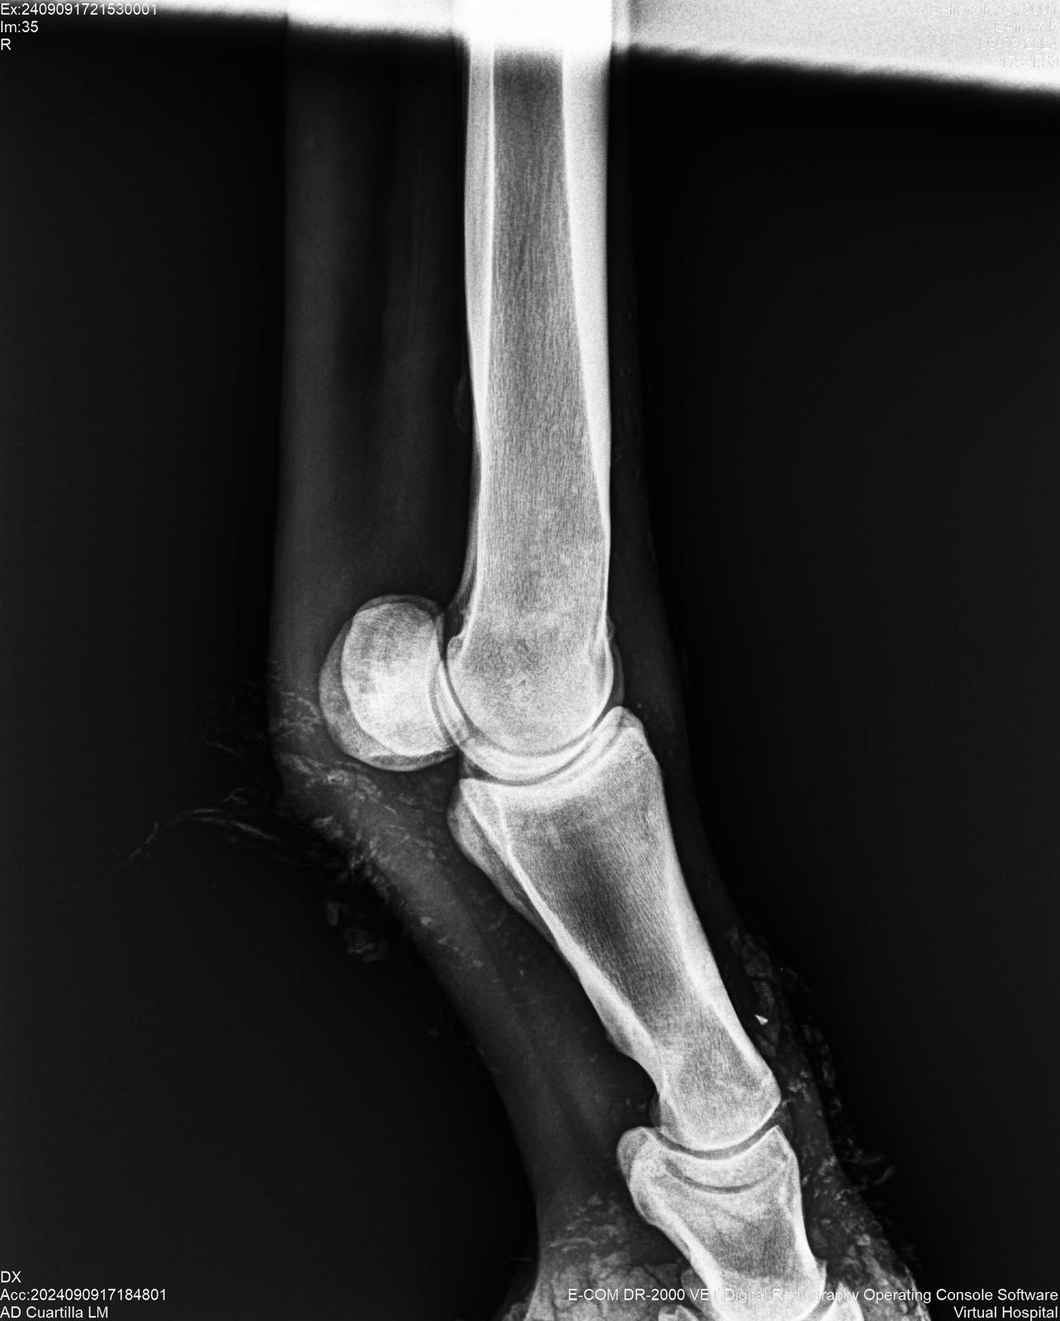

LOTE 44, SEÑORA K

Identificador: #291147-

Generacion 2022